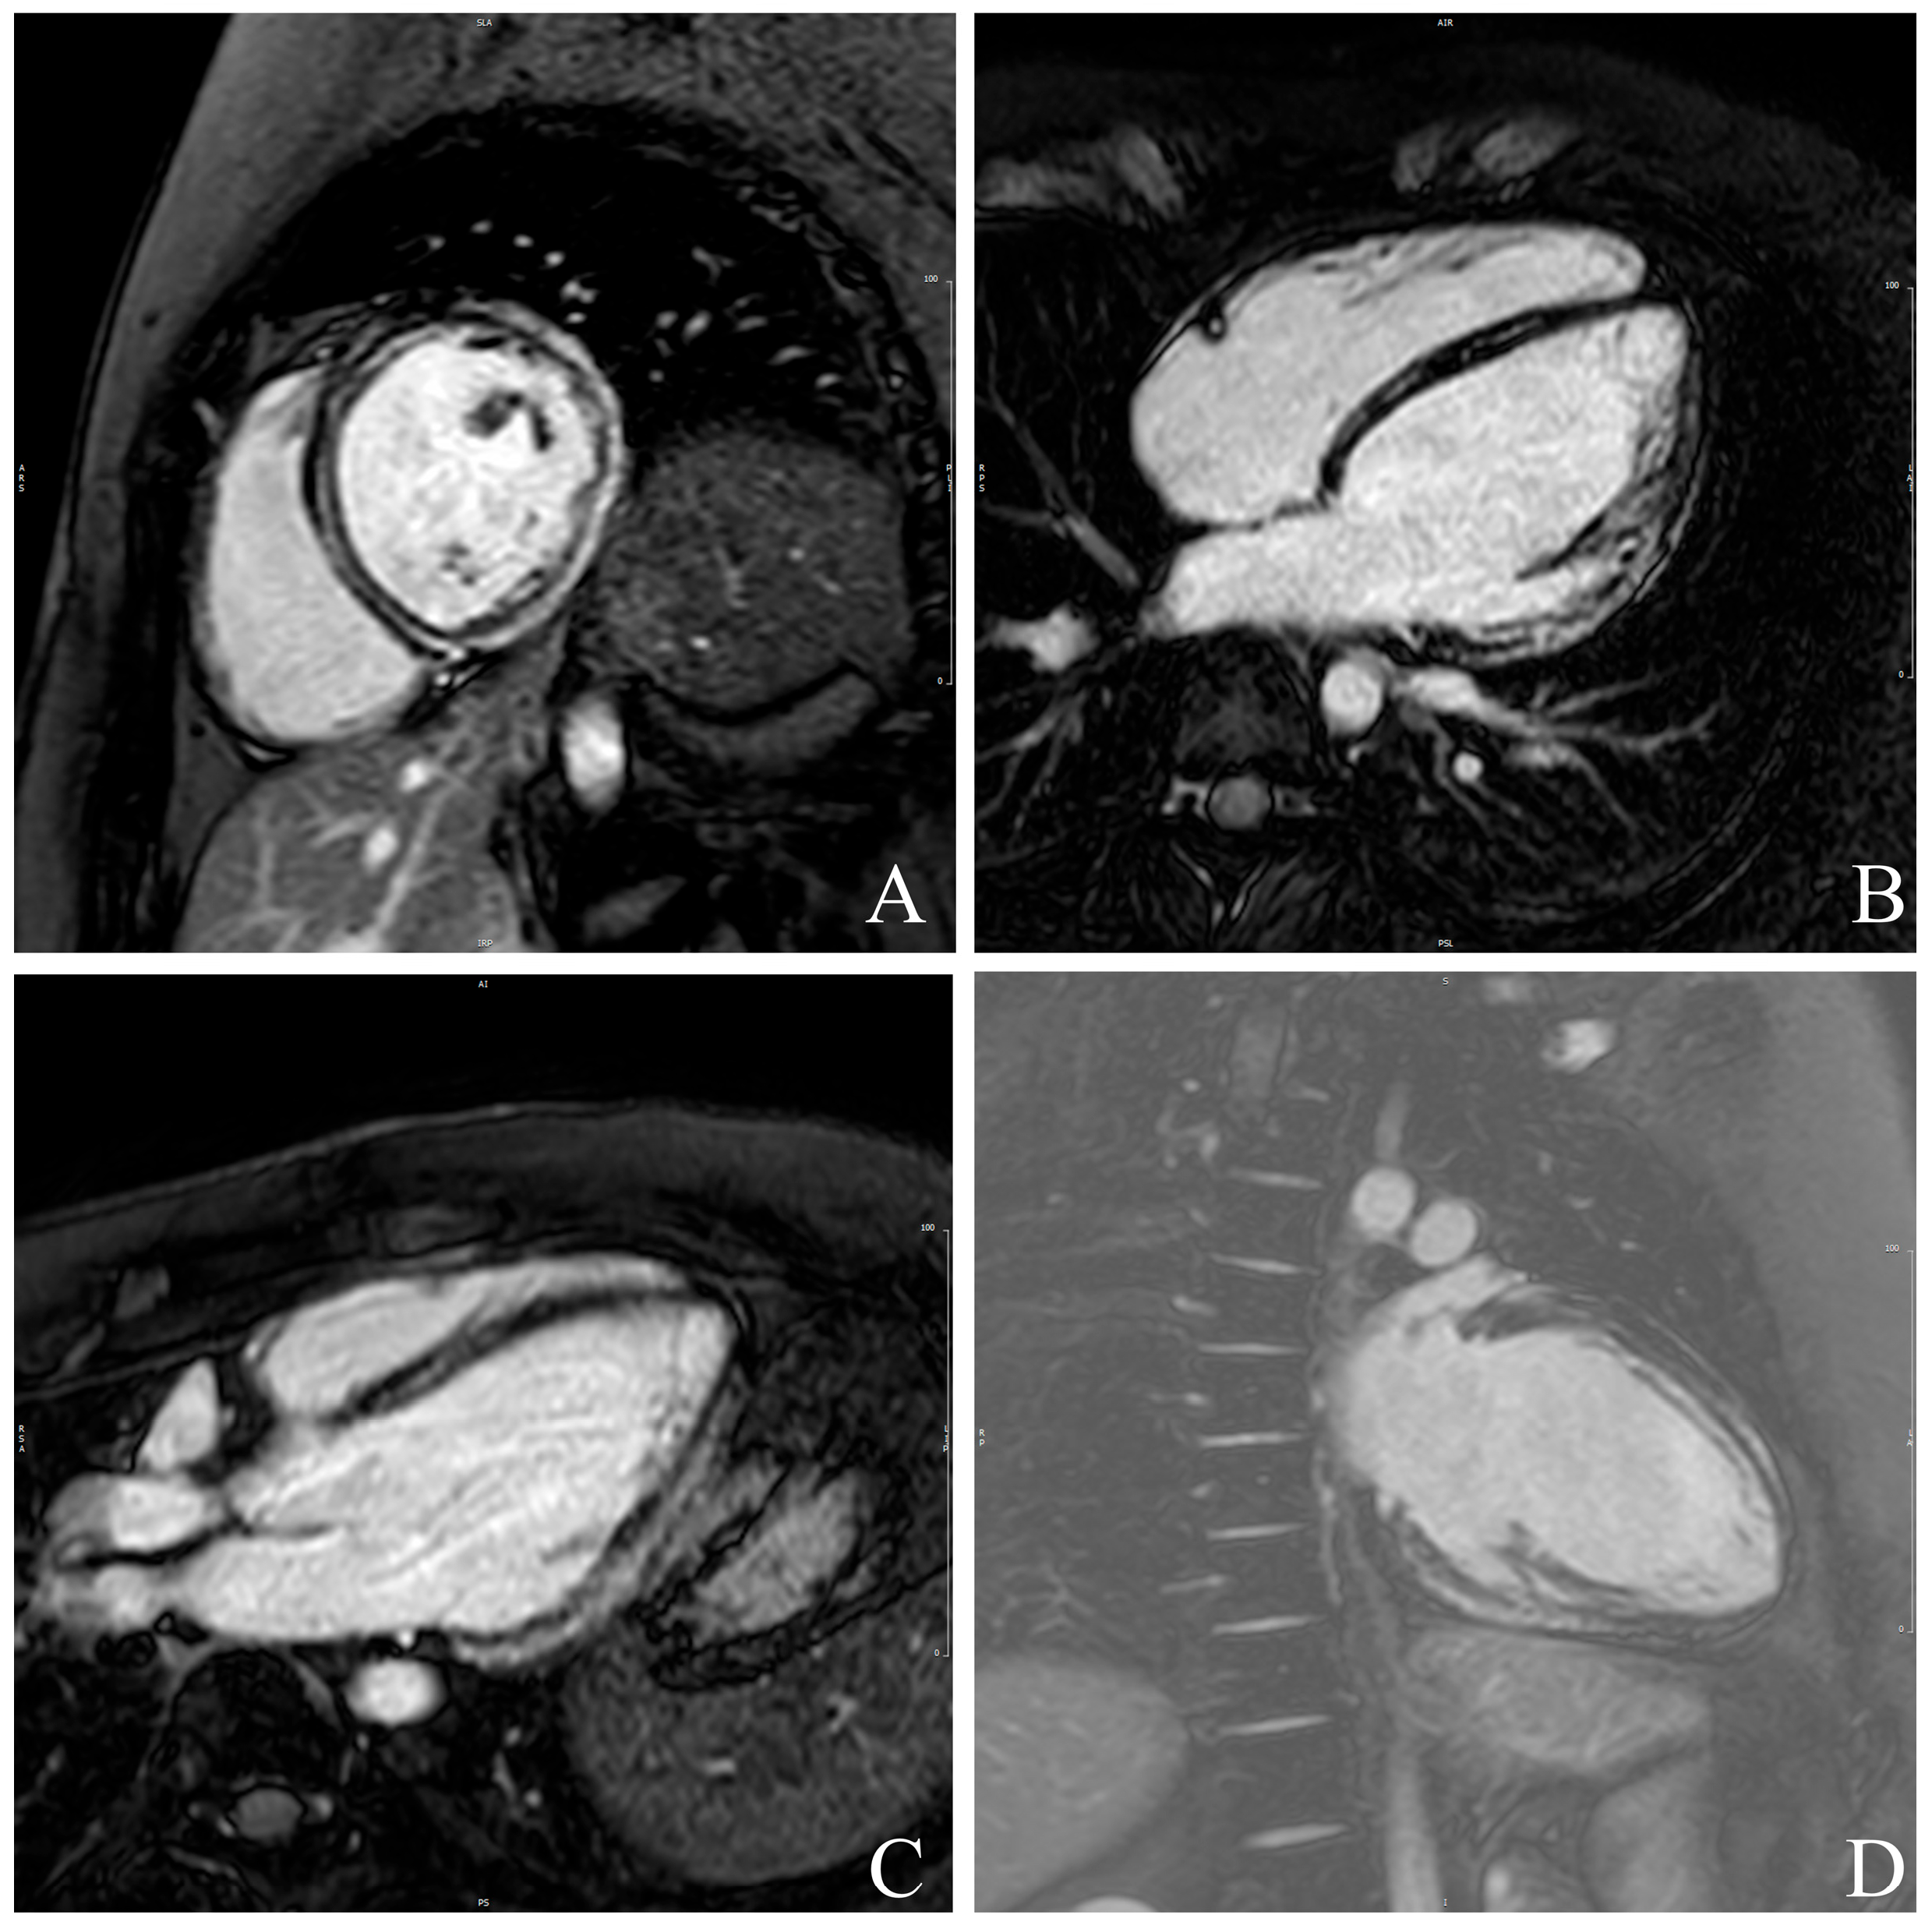

2.2. CMR Assessment

3.5. Association of Myocardial Mechanics with LGE